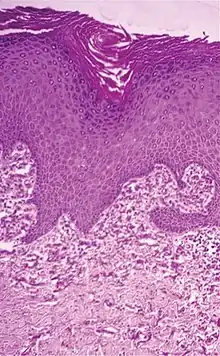

Elastosis perforans serpiginosa Degenerated elastic fibers and transepidermal perforating canals (arrow in image points at one of them)[11]

Perforating calcific elastosis Clumping of short elastic fibers in the dermis.[11]

Linear focal elastosis Accumulation of fragmented elastotic material within the papillary dermis and transcutaneous elimination of elastotic fibers.[11]